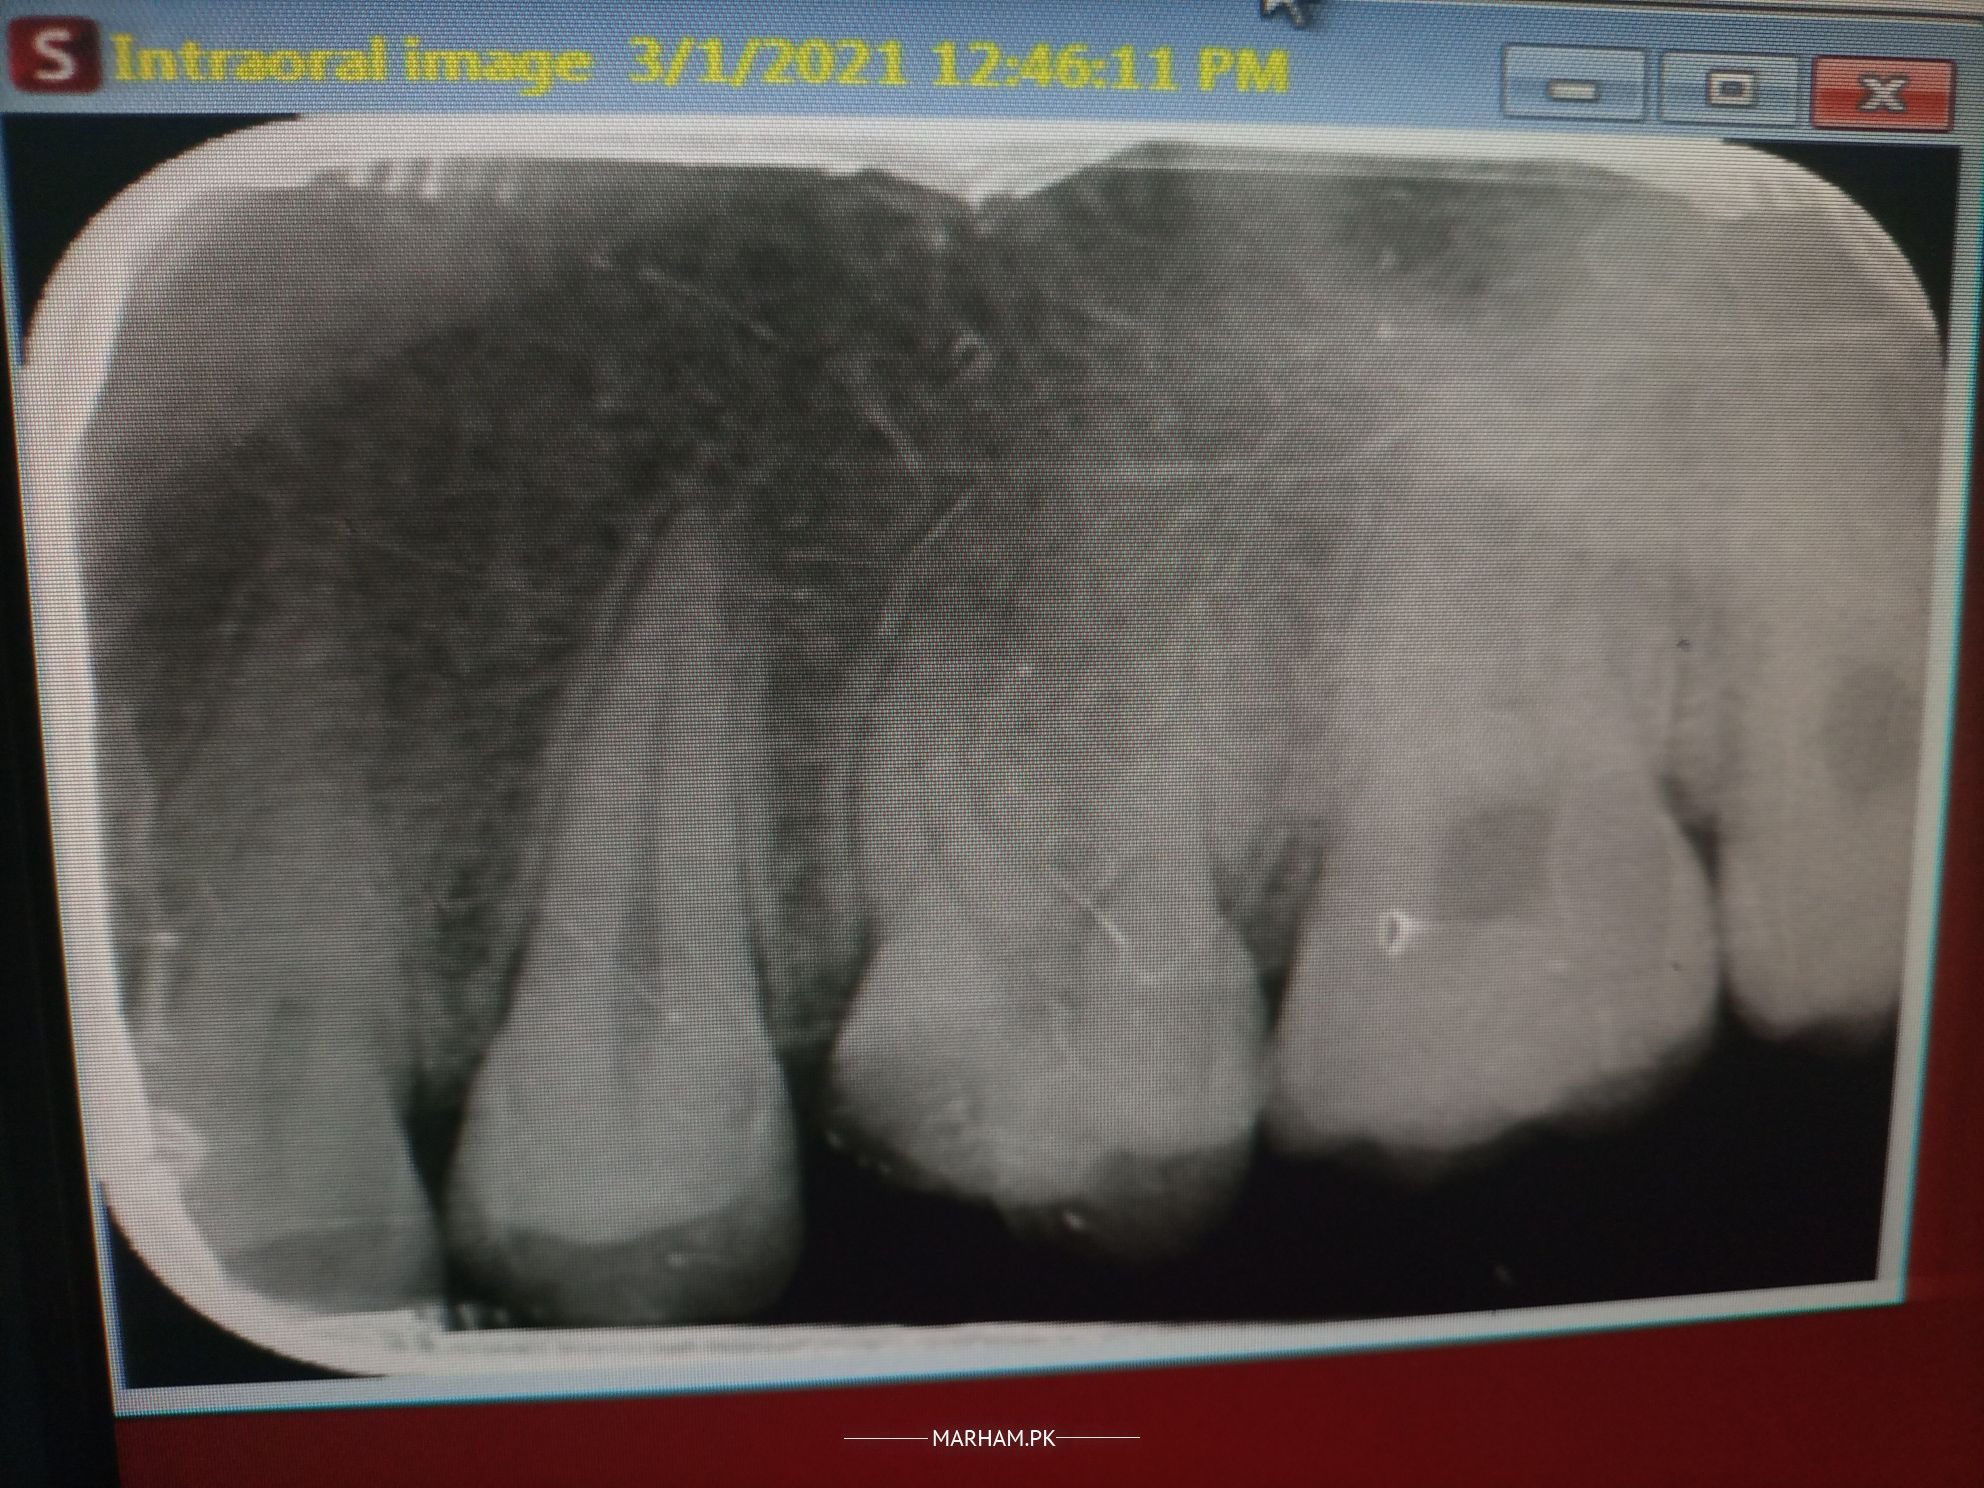

Can you tell me from the X ray what should i opt for my brother either RCT or Filling

The xray shows rct! You can book an appt with me through marham and get a a good treatment at a good you

brother root canal treatment lag rai hai ...

one best option is to be root canal treatment. but x ray should be be correlate with clinical symptoms

Root Canal Treatment!

RCT for sure

Rct is needed

Umm from the xray it does look like rct but if he dan visit us for a consultation we can check the tooth physically and see the extent of the decay and guide could just be a deep filling too but cant say for sure until checked the tooth.

Root canal treatment is necessary either pain is mild or X-ray show RCT treatment book your appointment with me through marham and get good treatment in reasonable amount